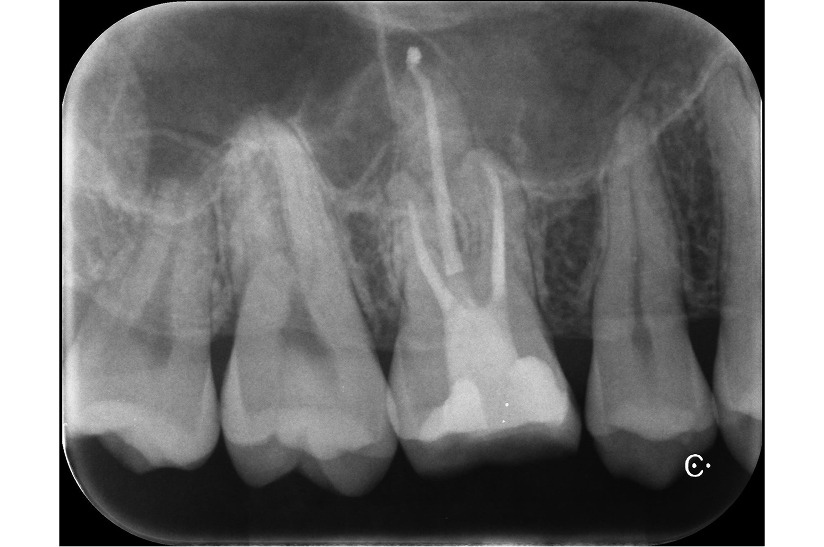

大臼歯の再根管治療を行った症例

タップで写真の拡大ができます。

Before&After(根管治療)

Before

Before&After(根管充填)

主訴

歯茎が腫れて、噛むと違和感がある

治療内容

再根管治療(大臼歯)

治療期間

1ヶ月

治療費用

165,000

治療の

リスク

処置中に歯肉縁下におよぶ重度のう蝕や破折を認めた場合、治療を中断する可能性があります。術後も症状が残る場合は追加の処置が必要になる可能性があります。